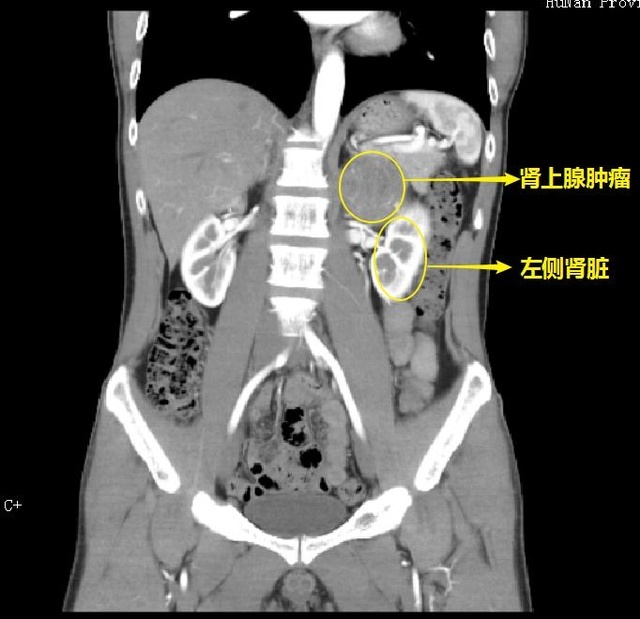

【检查结果显示,殷先生肾上腺肿瘤直径约7cm】

CT检查结果显示肿瘤直径约7cm,向上推压膈肌和脾脏,内侧推压腹主动脉,如果不及时采取手术治疗,肿瘤在体内如同一个定时炸弹,不仅会继续长大,随时还会使血压急剧升高并发心、脑血管意外危及生命。